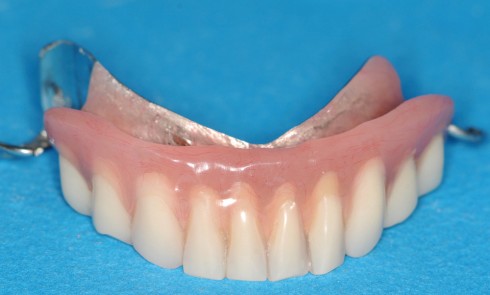

Article réservé à nos abonnés La réfection des bases prothétiques en prothèse partielle

Les traitements prothétiques par des prothèses partielles à châssis métallique sont et demeurent des thérapeutiques d’actualité et ce, malgré l’apport...